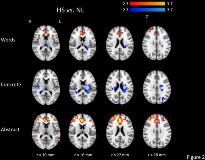

Rationale: Word recognition is a fundamental component of human language. Functional magnetic resonance imaging (fMRI) has shown that cortical networks involved in language processing are modified by temporal lobe epilepsy (TLE). However, the effect of TLE on the organization of cortical areas involved in visual word recognition and, in particular, semantic processing is unknown. In this study, we therefore examined the efficiency of lexical and semantic processing and associated brain activation using fMRI in subjects with left TLE.Methods: Twenty participants with left TLE (including 10 with hippocampal sclerosis, the HS group, and 10 without hippocampal sclerosis, the NL group) and 12 controls underwent an event-related fMRI analysis of word and nonword processing during a lexical decision task (LDT). Stimuli included concrete words, abstract words, and nonwords. Efficiency of processing was assessed by measuring the response times and accuracy of lexical decisions. Lexical and semantic processing were examined by comparing behavioural and imaging data associated with words and nonwords (lexicality) or with concrete and abstract words (concreteness), respectively.Results: During the LDT, all groups exhibited significant effects of lexicality and concreteness, such that response times were longer to nonwords than words, and to abstract words than concrete words (p < 0.001). Further, both TLE groups showed larger lexicality effects than did the control group in response times, but all groups achieved equivalent accuracy (p < 0.001). While the control group showed greater activation associated with word stimuli than nonword stimuli in a bilateral language network, both TLE groups showed greater activation for nonword stimuli than word stimuli, including greater activation of inferior frontal language areas (bilaterally in the HS group and left-lateralized in the NL group, Figure 1). The left TLE groups also exhibited differential activation patterns during the processing of abstract and concrete words compared to controls, and compared to each other (Figure 2). For abstract words, in particular, the HS group showed activation of frontal areas typically associated with executive functions whereas the NL group showed activation of more posterior semantic processing regions. Conclusions: These results suggest that left TLE is associated with altered functional organization of cortical networks involved in lexical and semantic processing but that this may not completely compensate for the inefficiency of the word recognition system in patients with left TLE. In addition, the organization observed varies as a function of hippocampal pathology. Specifically, with memory structures compromised in HS, these patients must recruit more frontal areas in order to judge lexicality for abstract words.